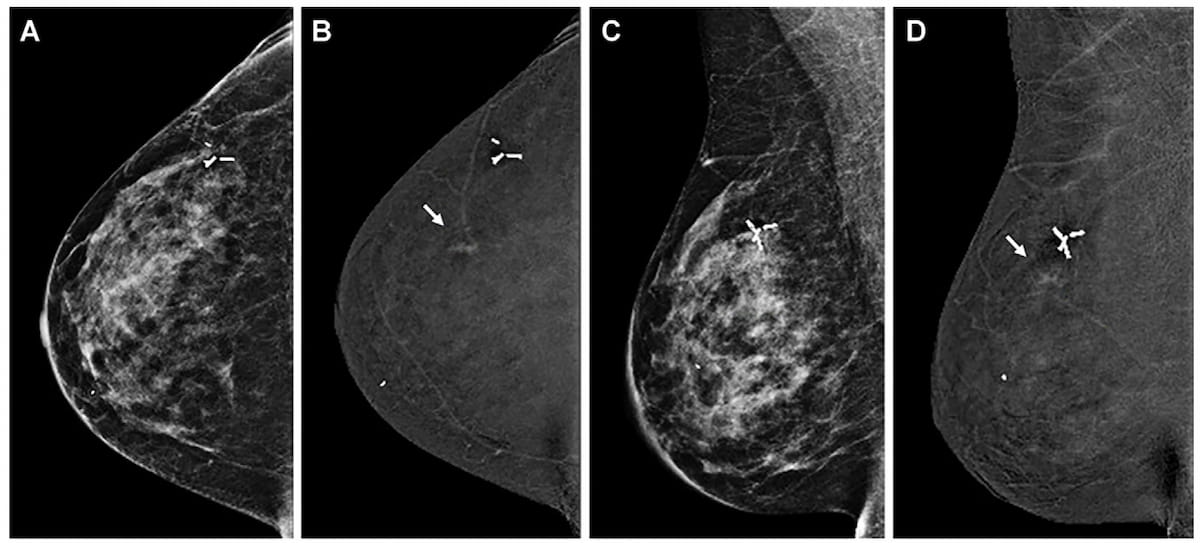

In a study involving over 272,000 breast cancer screening exams, digital breast tomosynthesis (DBT) had a higher breast cancer detection rate and a lower rate of advanced cancer presentation at the time of diagnosis in comparison to digital mammography.

Digital breast tomosynthesis (DBT) had a significantly higher cancer detection rate (CDR) in comparison to two consecutive post-DBT rounds of digital mammography, according to a new secondary analysis of the Malmo Breast Tomosynthesis Screening Trial (MBTST).

In a study of asymptomatic women at elevated risk for breast cancer, digital breast tomosynthesis (DBT) demonstrated equivalent sensitivity to full-field digital mammography (FFDM) for three out of four reviewing radiologists and detected no additional cancers beyond those detected with FFDM.